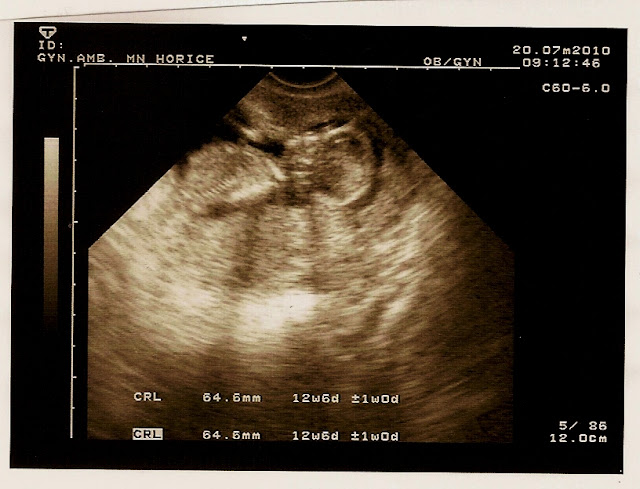

31.7.2010

První snímek plodu našeho potomka!!! Pohlaví zatím neznámé a předpokládaný termín narození je koncem ledna 2011.